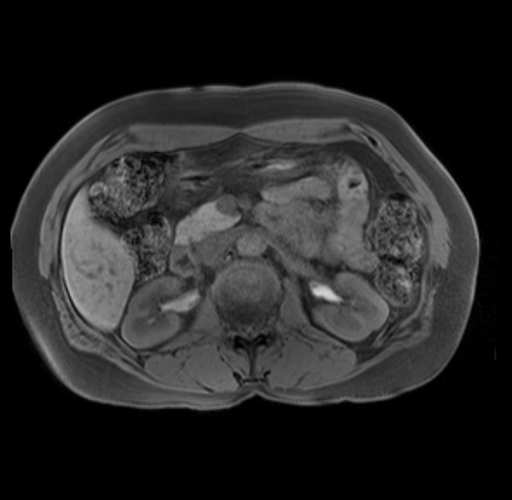

Imaging Analysis

Look through the patient's CT scan to identify any areas of concern for the necessary procedure.

Based on your CT findings, which issue(s) are present and would give reason for "planned slowing down moment(s)" in this case?